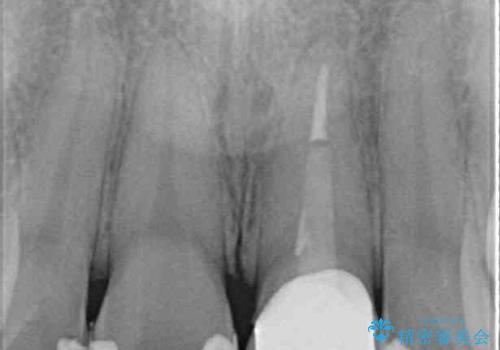

出っ歯に仕上がってしまった前歯 セラミッククラウンの作り替え

- 以前治療した時から、前歯のセラミックが張り出しているのが気になるとのことで来院された患者様です。

作り替えるべきが悩みましたが、どうしても気になるとのことで、処置を行うこととしました。

前歯1歯でのオールセラミッククラウンでは、オーダーメイドタイプのクラウンを選択していただき、周辺の歯と色調を合わせるようにするのですが、今回は既製タイプを選択されました。